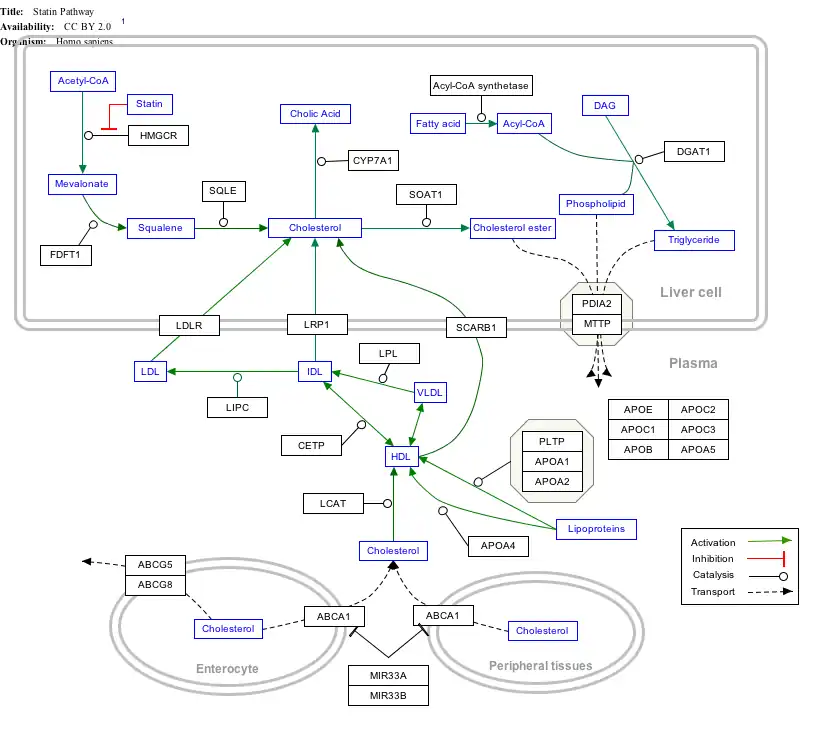

Interactive pathway map

Click on genes, proteins and metabolites below to link to respective articles.[§ 1]

- ↑ The interactive pathway map can be edited at WikiPathways: "Statin_Pathway_WP430".